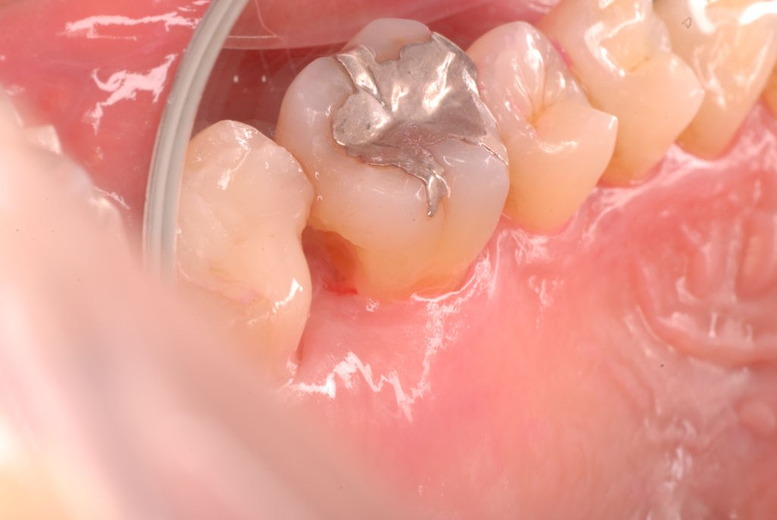

色々不満な入れ歯です。

発音や見える金属が気になるようです。

ご自分でやられても歯茎から血が出ないと話をされていましたが、私がブラシを当てると悲惨な状態であることがわかりました。